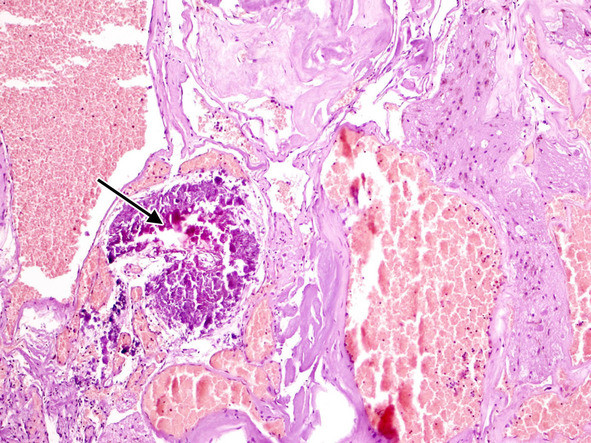

При рутинном исследовании в световом микроскопе (срезы толщиной 5 мкм, окраска гематоксилином и эозином, при необходимости – докрашивание по Ван-Гизон и Маллори) каверномы представляют собой конгломерат тонкостенных полостей разнообразной неправильной формы, выстланных эндотелием и разделенных соединительнотканными перегородками. Соединительная ткань перегородок может быть представлена как тонкими коллагеновыми волокнами, так и грубоволокнистой фиброзной тканью с различной степенью дистрофических изменений. Характерным признаком является отсутствие в стенах каверн гладкомышечных клеток и эластических волокон, а также мозговой ткани между кавернами (рис. 11) (2, 236, 299, 333).

Полости, образующие каверному, могут быть заполнены жидкой кровью либо тромбами в различной стадии формирования (рис. 13).

В ткани КМ могут быть обнаружены участки кальцификации, гиалиноза стенок (рис. 14).

Довольно часто в строме встречаются признаки повторных кровоизлияний в виде остатков гематом различной давности. По периферии каверномы часто можно обнаружить фрагменты капсулы, типичной для хронической гематомы (рис. 15).

Рис. 11. Кавернозная мальформация «классического» типа —конгломерат сосудистых полостей различной формы и размеров, выполненных кровью.Ув. х 100

Рис. 13. Тромбоз и склероз сосудистых полостей в «классической» кавернозной мальформации.Ув. х 200

Рис. 14. Кальцификат (стрелка) и склеротические изменения в стенках сосудистых полостей. Ув. х 100